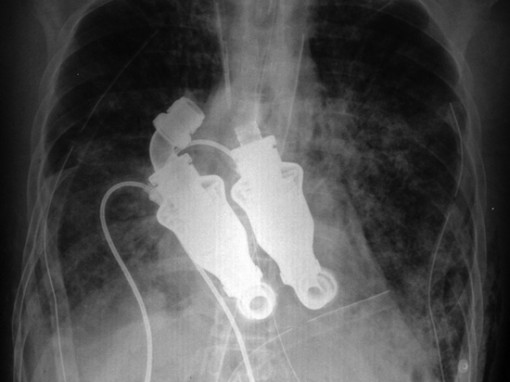

Keinosydän pitää potilaan hengissä ilman pulssia